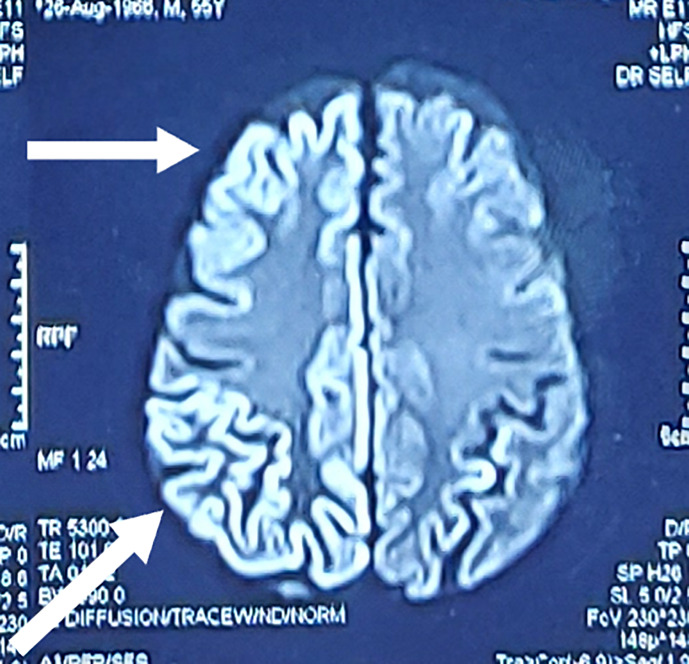

Case presentation: We hereby present the case of a 55-year-old man with a history of diabetes mellitus (potential impact on COVID-19 severity discussed in the supplementary material) presenting with altered sensorium, swelling in the left eye, and involuntary jerky limb movements. Neurological examination revealed neck rigidity, myoclonic jerks, and an extensor plantar response. Brain magnetic resonance imaging (MRI) was performed, which revealed cortical enhancement in the bifrontal, temporal, and occipital lobes. Rapid progression of myoclonus, altered sensorium, and cortical enhancement on MRI suggested Creutzfeldt-Jacob disease. After a thorough workup, the diagnosis was COVID-19 encephalitis with rhino-orbital mucormycosis. The treatment regimen consisted of adequate glycemic control, remdesivir injection, intravenous and retroorbital liposomal amphotericin, and levetiracetam. The patient's condition improved, and he was eventually discharged.